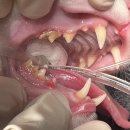

• 뿌리동물병원 치과센터 | 고양이 치주염, 송곳니 골염으로 인한 수원 뿌리동물병원 고양이 치과 예진 후기 + 신부전 초기 발견?!

🐈 ​ 더이상은 미룰 수 없었던 춘장이의 발치수술..🦷 괜찮다는 동물치과전문병원 찾고 찾아 드디어 방문하게 된 수원의 뿌리동물병원 예진 후기! ​ ​ ✔️춘장이의 이빨 상태와 발치 수술을 결정하게 된 계기 ​ 23년도쯤부터 춘장이 왼쪽 윗 송곳니의 잇몸이 점점 부풀어오르더니 색도 점점 빨개졌다.. ​ 양치를 매일같이 해줘도...

ᕷ ᴘɪᴋᴏᴘɪᴋᴏ | ʙᴀʙʏ&ᴅᴀɪʟʏ ᕷ(2025-10-11 10:50:00)